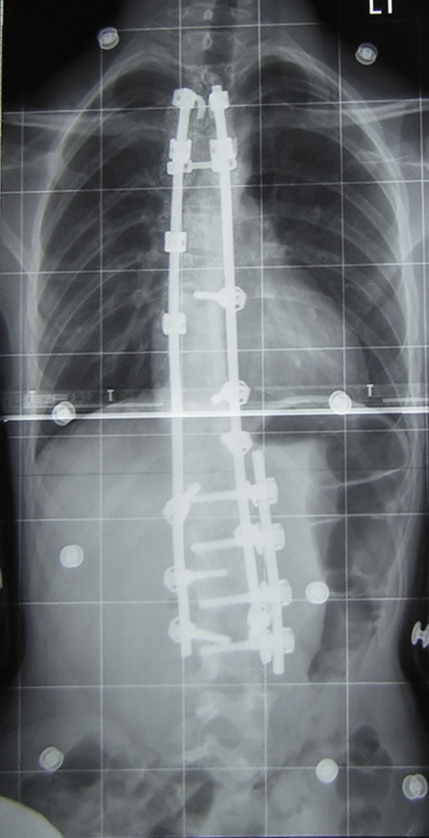

| Описание | SummaryThis is an anterior-posterior X-ray of a case of adolescent idiopathic scoliosis post-fusion - specifically, my spine. There was originally a thoracic curve of 30° and a lumbar curve of 53° (Cobb angle - see scoliosis) and these curves have been reduced to less than 15° each. This was taken at the Royal National Orthopaedic Hospital. The largest curve (53°) is of a magnitude typically near the lower surgery boundary, although many factors decide whether surgery is necessary on a scoliosis case. This x-ray was taken almost a year after this x-ray was taken of the same spine pre-op: <figure class="mw-halign-left" typeof="mw:File/Thumb">[1]<figcaption></figcaption></figure> The spine has been fused with Synergy spinal instrumentation [1] [2] (page 2) during an anterior and posterior fusion. Vertebrae T1-L3 have been fused using a combination of rods, screws and hooks, and bone graft. |